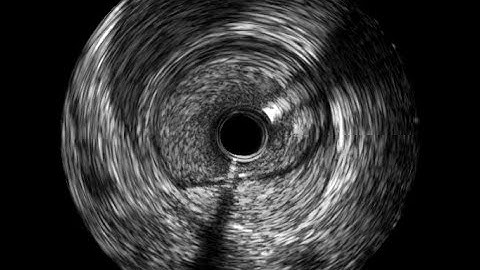

IVUS: Identify DISSECTION and intramural HEMATOMA